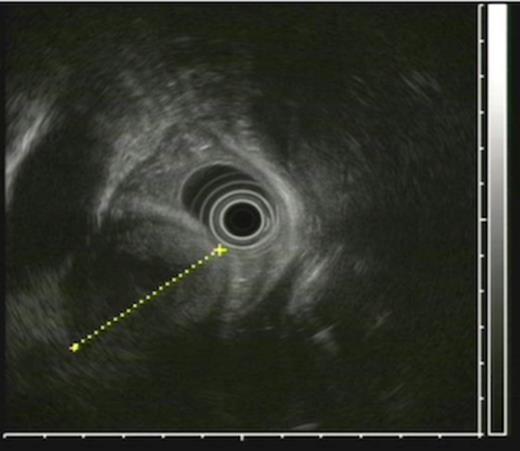

An endoscopy performed four years post-operatively demonstrated two atypical acute gastric ulcers in the distal stomach (figure 1), which were treated with a heat probe (figure 2). Two days later she presented as an emergency in hypovolaemic shock following a large volume haematemesis (haemoglobin of 40g/l). An urgent upper gastrointestinal endoscopy revealed a visible vessel at 35 cm forming part of an expansive mass within the gastric conduit. EUS demonstrated a heterogeneous mass indenting the gastric conduit, containing a strong Doppler signal (figure 3). An urgent computerised tomography (CT) angiogram revealed a Type-A thoracic aortic aneurysm with an enteric fistula (figure 4). The saccular aneurysm of the thoracic aorta was embedded in the gastric conduit. A 28x16cm Valiant® (Medtronic Ltd, Minneapolis, USA) stent was placed in the descending thoracic aorta with good occlusion of the aneurysm. The patient made an excellent recovery and was discharged on the seventh day post stenting.